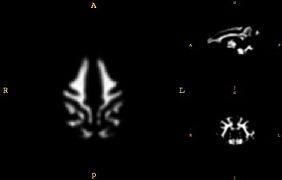

• Develop a juvenile WM/GM/CSF atlas from normal subject images.

• The atlas construction procedure was adapted from Automatic brain segmentation in rhesus monkeys; M. Styner, R. Knickmeyer, S. Joshi, C. Coe, S. J. Short, and J. Gilmore. Proc SPIE Vol 6512 Medical Imaging 2007, pp 65122L-1 - 65122L-8.

Images